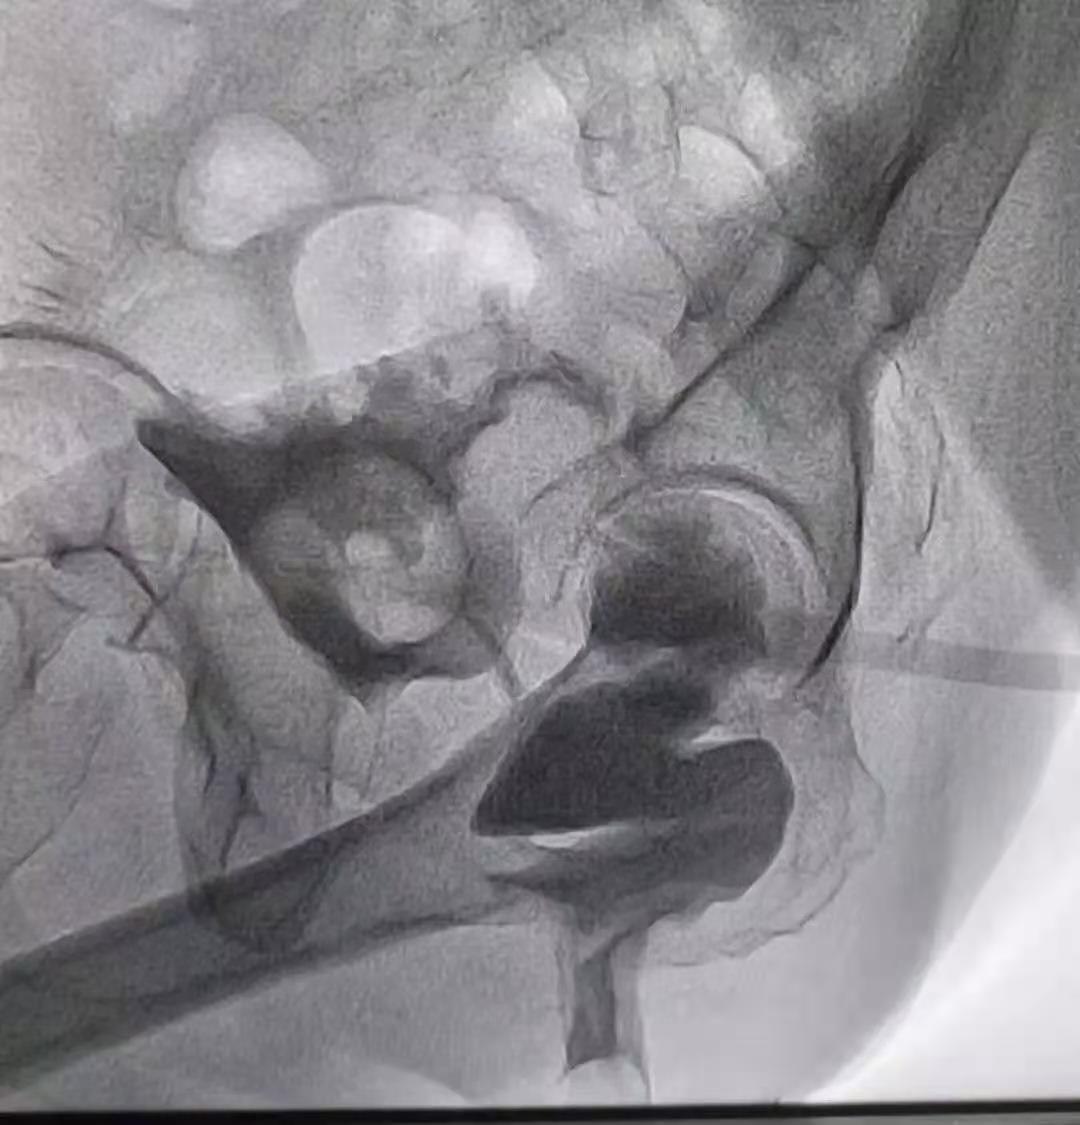

2、脓肿引流

用穿刺针经皮穿刺,并在 CT 扫描或超声内镜的引导下,对较大脓肿进行引流。如果排脓液有所帮助,患者可一直住院,直到症状已缓解,可以恢复软质饮食。如果引流不起作用,则需手术。